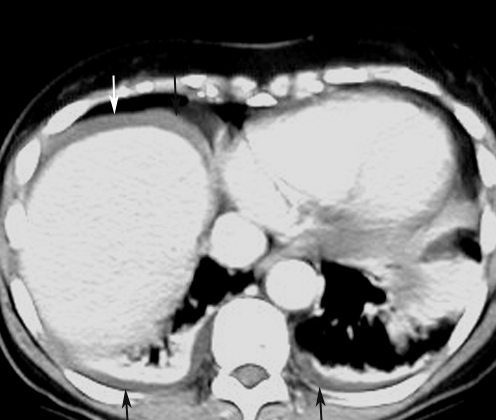

CT: Highly accurate

Signs: